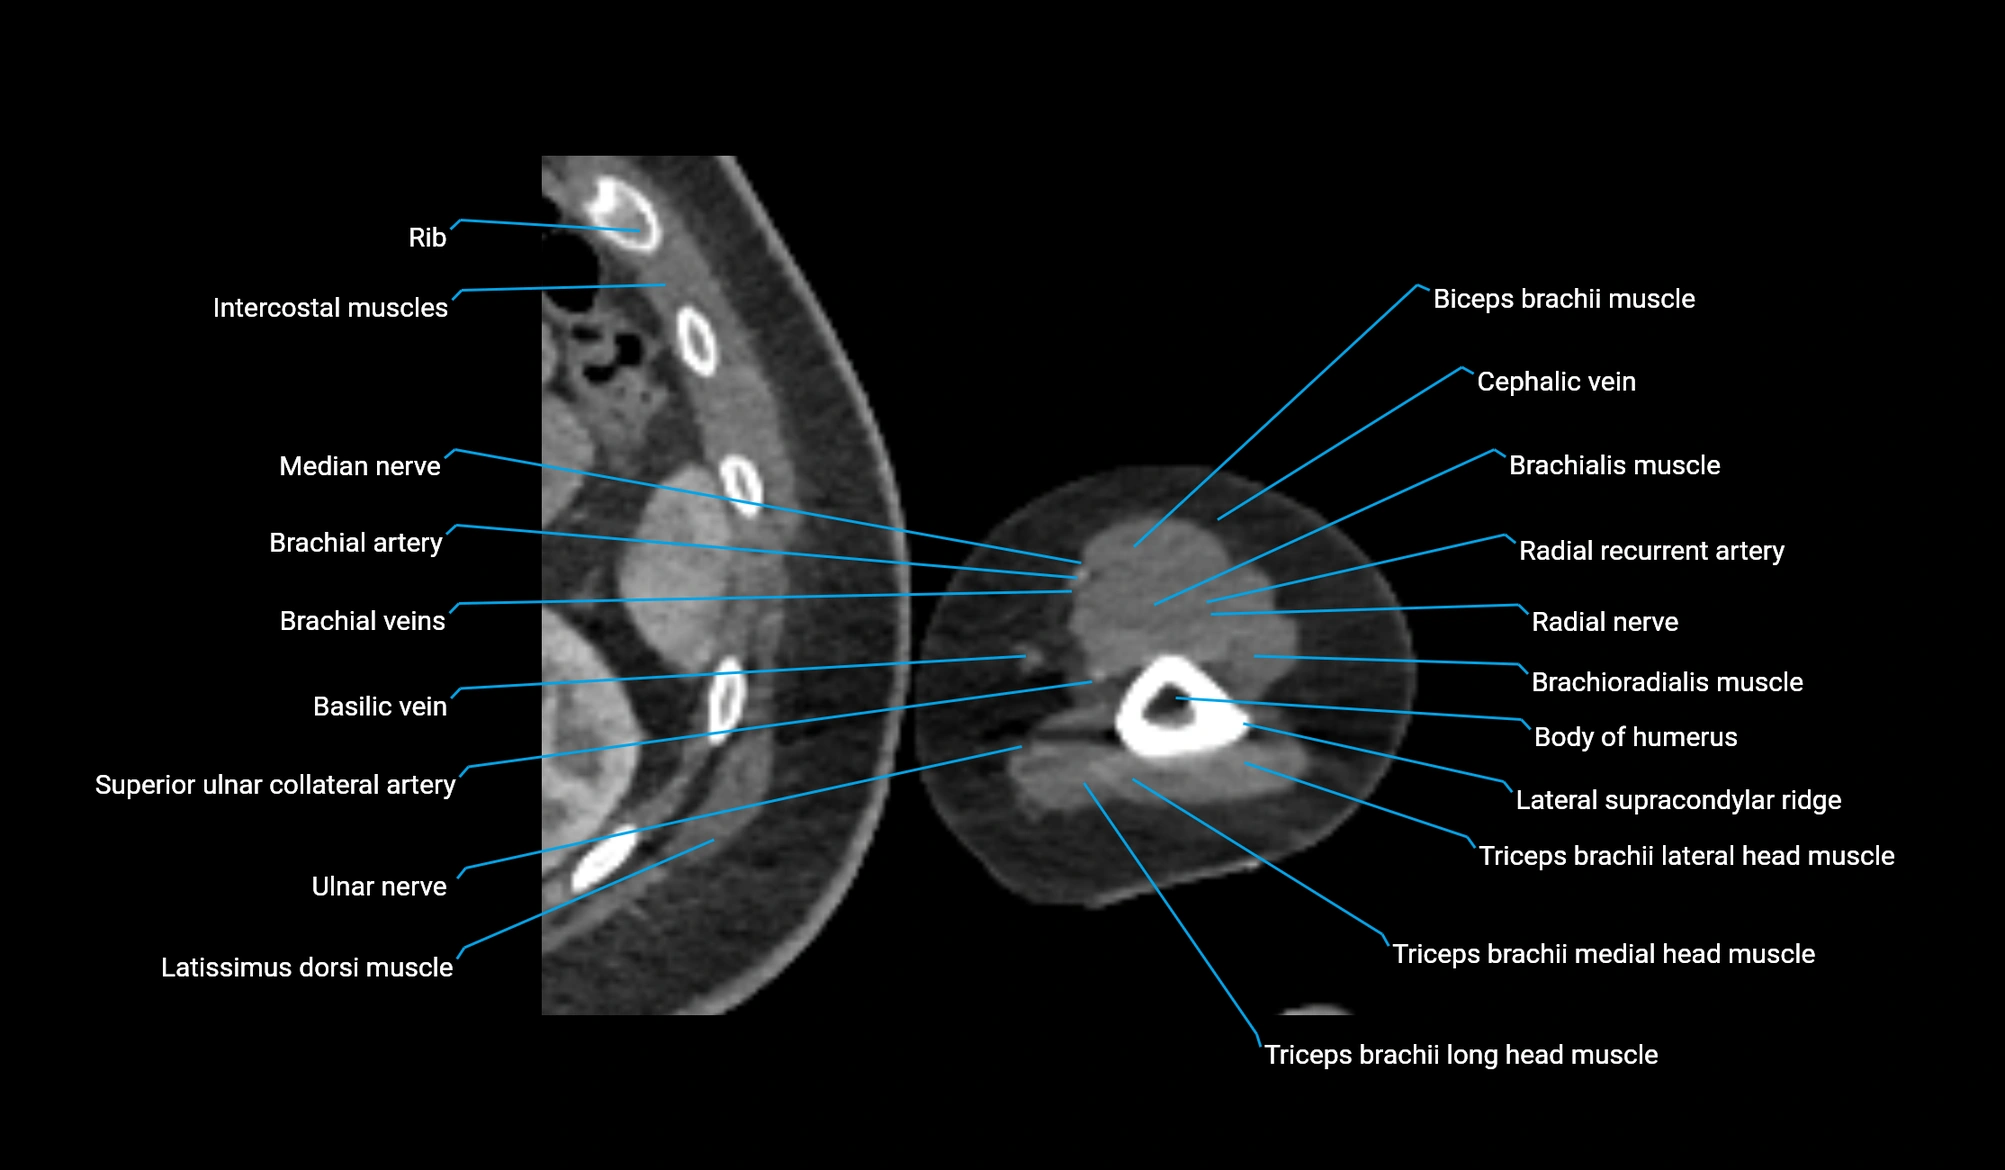

- Body of humerus

- Brachialis muscle

- Brachioradialis muscle

- Cephalic vein

- Lateral supracondylar ridge

- Long head of triceps brachii muscle

- Lateral head of triceps brachii muscle

- Medial head of triceps brachii muscle

- Radial nerve

- Radial recurrent artery